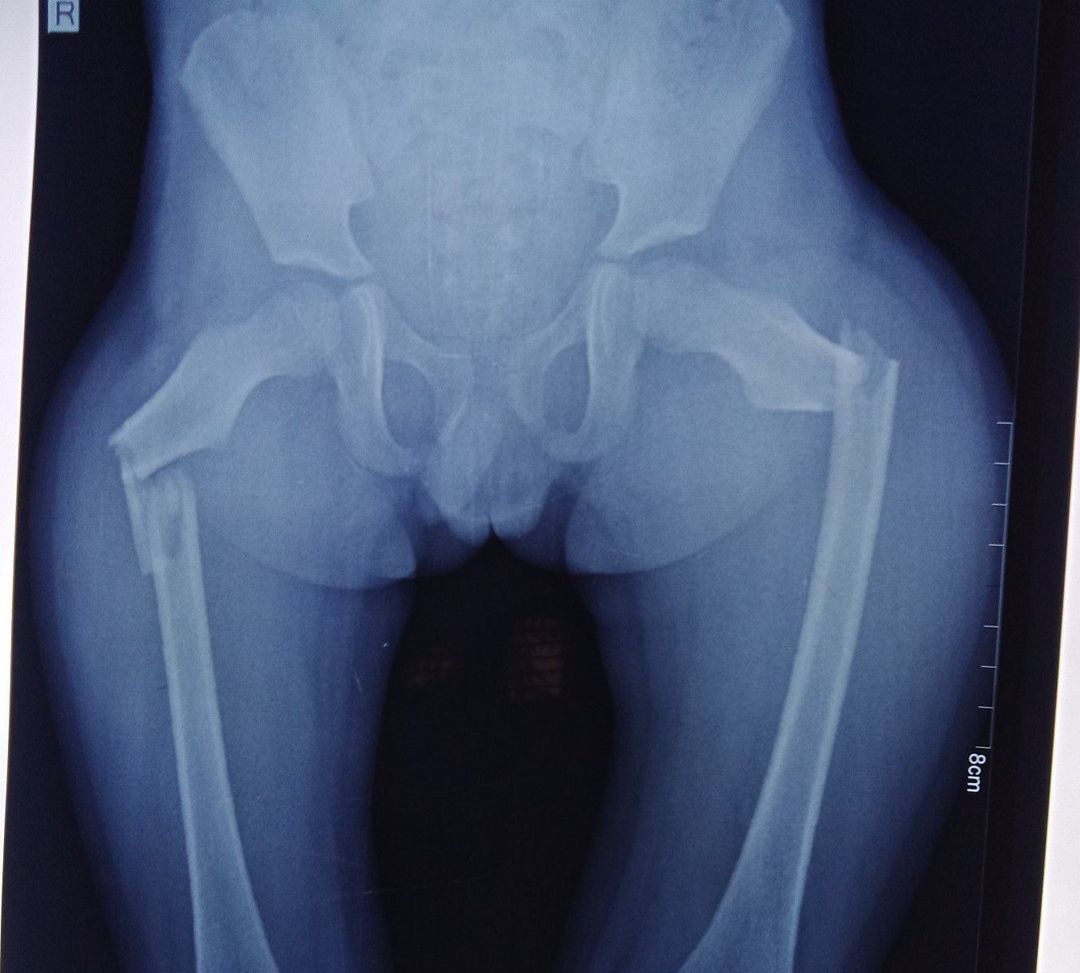

Fracture

Orthopedics